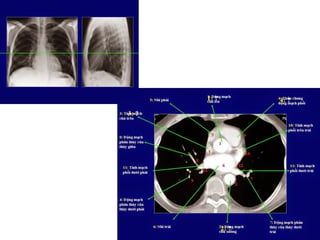

Giải phẩu CT ngực – các mạch máu

lớn.

SVC: tĩnh mạch chủ trên.

Aortic arch: cung đm chủ

Pulmonary artery: đm phổi

Main sterm bronchus: phế quản gốc